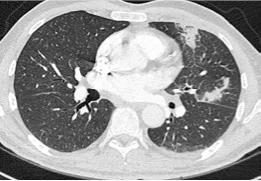

Mujer de 64 años, que acude para realización de ablación de venas pulmonares (VVPP) mediante electroporación por fibrilación auricular (FA) permanente tras tres ablaciones que no resultaron efectivas. Destacan los siguientes antecedentes personales de interés:

■ Fibrilación auricular (FA) paroxística recurrente (2014) con sintomatología de grado III según la clasificación de la European Rhytm Association (EHRA), CHA2DS2-VA2 1 punto (HTA) anticoagulada con Rivaroxabán 20 mg y con realización de tres ablaciones (2016, 2020 y 2021). Ausencia de cardiopatía estructural.

■ Síncope de perfil cardiogénico por probable disfunción sinusal farmacológica (2023).

ABLACIÓN DE VENAS PULMONARES MEDIANTE ELECTROPORACIÓN PARA EL CONTROL DEL RITMO EN LA FIBRILACIÓN AURICULAR PERMANENTE: A LA CUARTA VA LA VENCIDA

- Ecocardiograma: Presenta aurículas y ventrículos con tamaño y función normales con fracción de eyección del ventrículo izquierdo (FEVI) del 60%. No se visualiza derrame pericárdico.

EVOLUCIÓN